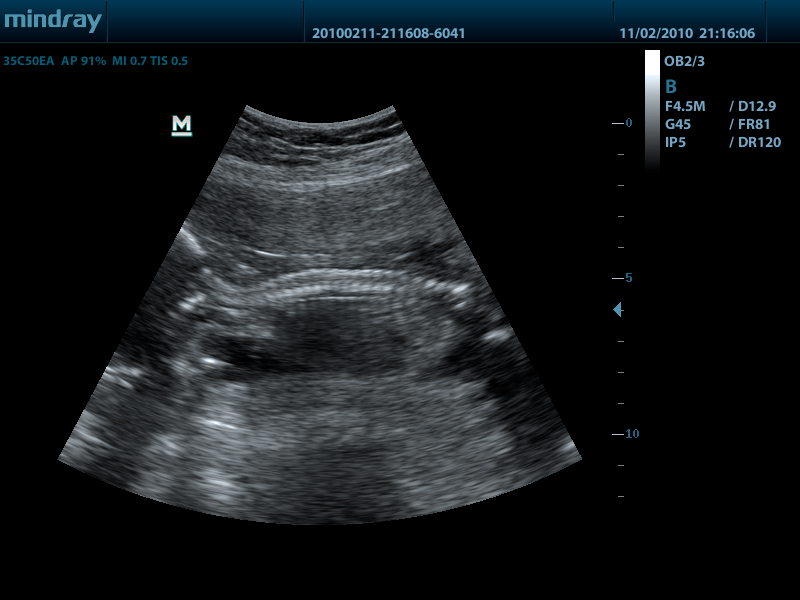

- Конвексный датчик 35C50EA, 1.7 - 6.0 МГц, радиус кривизны 50 мм